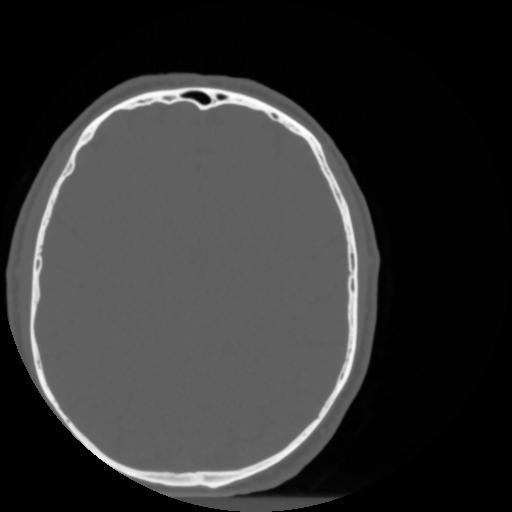

4 CEREBRO,,Vol,0.5,CEREBRO,,